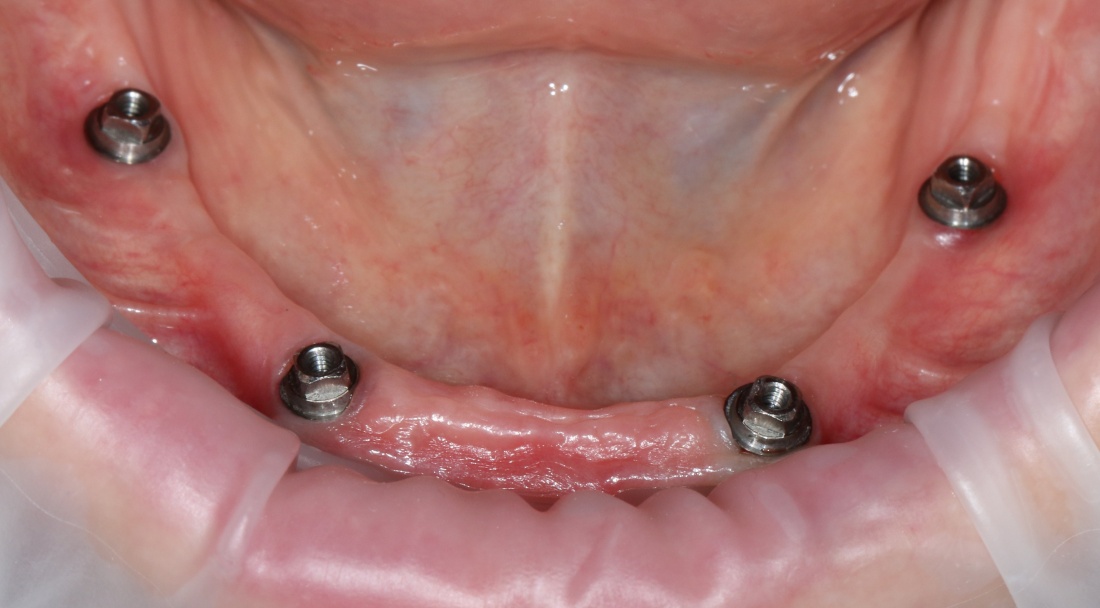

Самый простой пример — это хронический пародонтит, в условиях которого немедленная имплантация представляет определённые риски с точки зрения сохранения окружающих имплантат тканей:

Именно поэтому к широко рекламируемым методам «всё-на-четырёх» или All-On-4 нужно относиться крайне осторожно — иногда лучше решать такие клинические задачи не быстро и за один раз, а в несколько этапов, последовательно и безопасно.